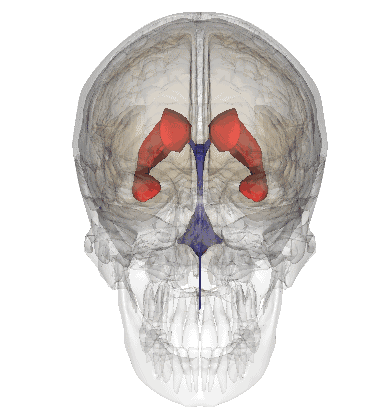

2.脑室系统